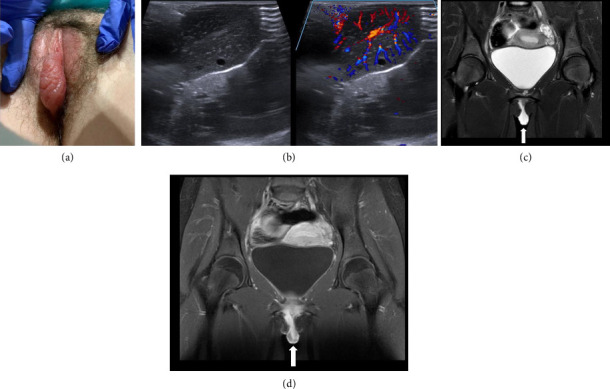

背景:文献描述青少年阴唇的放射影像缺乏,可能导致误诊和不必要的医疗护理。病例:两名青少年患者表现为突发性单侧小阴唇增大,并进行了多次影像学检查,发现了一个离散的肿块。一名患者在急诊室长时间住院后被诊断为口腔溃疡,另一名患者在麻醉下接受肿块切除检查,发现小阴唇卷曲。结论:由于缺乏关于预期结果的文献,青少年小阴唇肿大可能在放射成像上被误认为是一个离散的肿块。临床相关性和了解年龄相适应的病因的非感染性唇肿是至关重要的,以避免不必要的医疗治疗和程序。

Background: Literature describing radiologic imaging of the adolescent labia is lacking and may lead to misdiagnoses and unnecessary medical care. Cases: Two adolescent patients presented with sudden-onset unilateral labia minora enlargement and underwent multiple imaging modalities which identified a discrete mass. One patient was diagnosed with aphthous ulcers after a prolonged emergency department stay, and the other underwent an exam under anesthesia for mass removal and was found to have an elongated labia minora rolled into itself. Conclusion: Labia minora enlargement in adolescents can be significant and may be mistaken for a discrete mass on radiologic imaging given a lack of literature on expected findings. Clinical correlation and understanding of age-appropriate etiologies of noninfectious labial swelling is crucial to avoid unnecessary medical therapies and procedures.